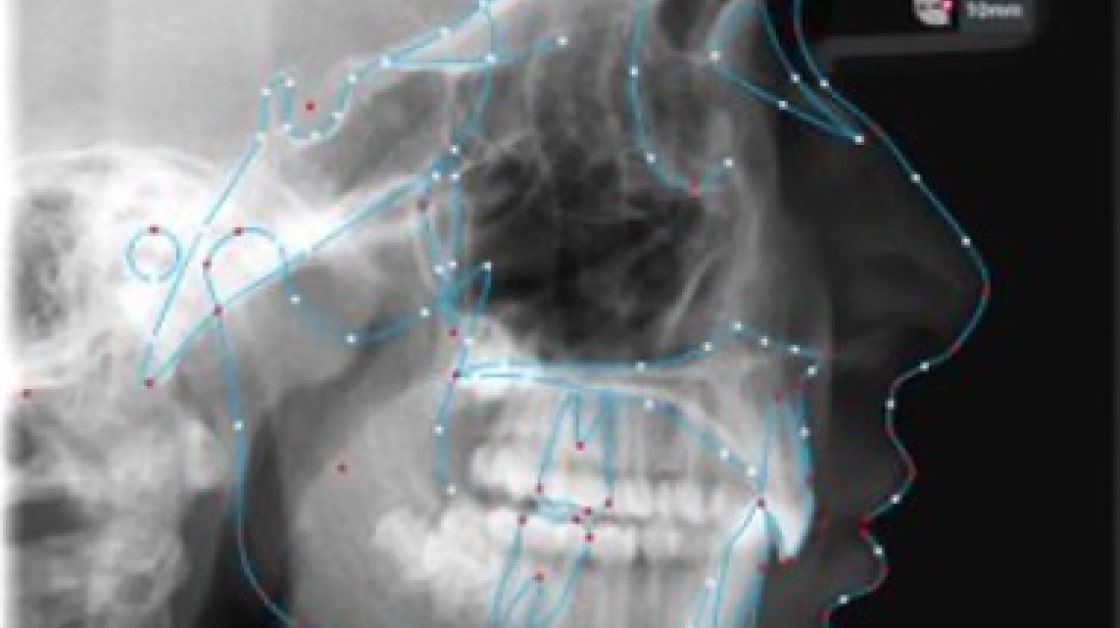

Tracing

With tracing algorithms, we ensure that all dental landmarks are accurately and precisely traced on digital models. This feature allows for more accurate and efficient treatment planning and diagnosis, leading to better patient outcomes.